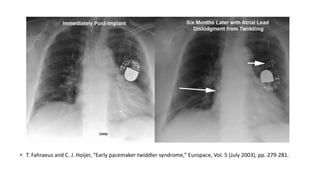

A 61-year-old man presented with worsening right thoracic pain and dyspnea three days after being discharged from cardiology following pacemaker implantation for sick sinus syndrome. A 60-year-old woman with an implanted pacemaker presented with dizziness and fainting. A 77-year-old woman who had a pacemaker implanted for symptomatic sinus bradycardia presented one week later with continuous chest pain. An elderly patient presented 6 months after pacemaker implantation with a recurrence of exertional shortness of breath.